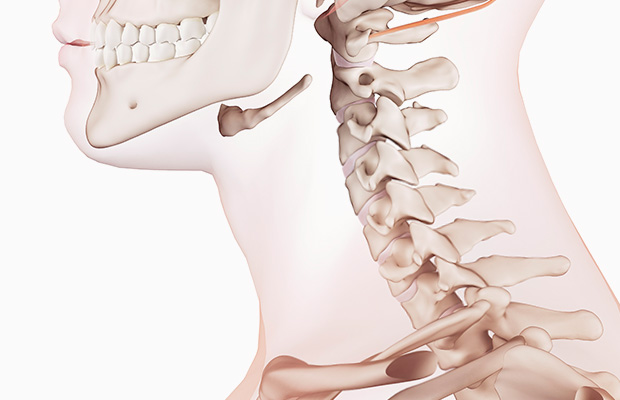

우선 목디스크란 목뼈 사이의 디스크가 깨지거나 상해 일어나는 질환을 의미합니다. 디스크는 척추뼈 사이에서 충격을 흡수하고 신경을 보호해주는 역할을 하는데, 디스크가 손상되면 신경이 압박되어 통증, 저림, 마비 등의 증상이 보여집니다.

목디스크의 원인은 다채롭지만, 대표적인 원인은 외상입니다. 외상은 교통사고, 스포츠 부상, 낙상 등 많은 종류의 이유로 생겨날 수 있습니다. 게다가, 틀린 자세, 과한 스트레스, 노화 등이 목디스크의 발생 위험을 높입니다.

목디스크의 증상은 여러종류가 있으며 환자마다 그 증상이 같지않게 생겨날수 있습니다. 최고 흔한 증상으로는 목의 통증입니다. 목의 통증은 목 뒤쪽, 어깨, 팔, 손까지 뻗쳐서 일어날 수 있습니다. 거기에다가, 저림, 마비, 감각 이상, 손발의 힘 저하 등의 증상이 발생할 수 있습니다.